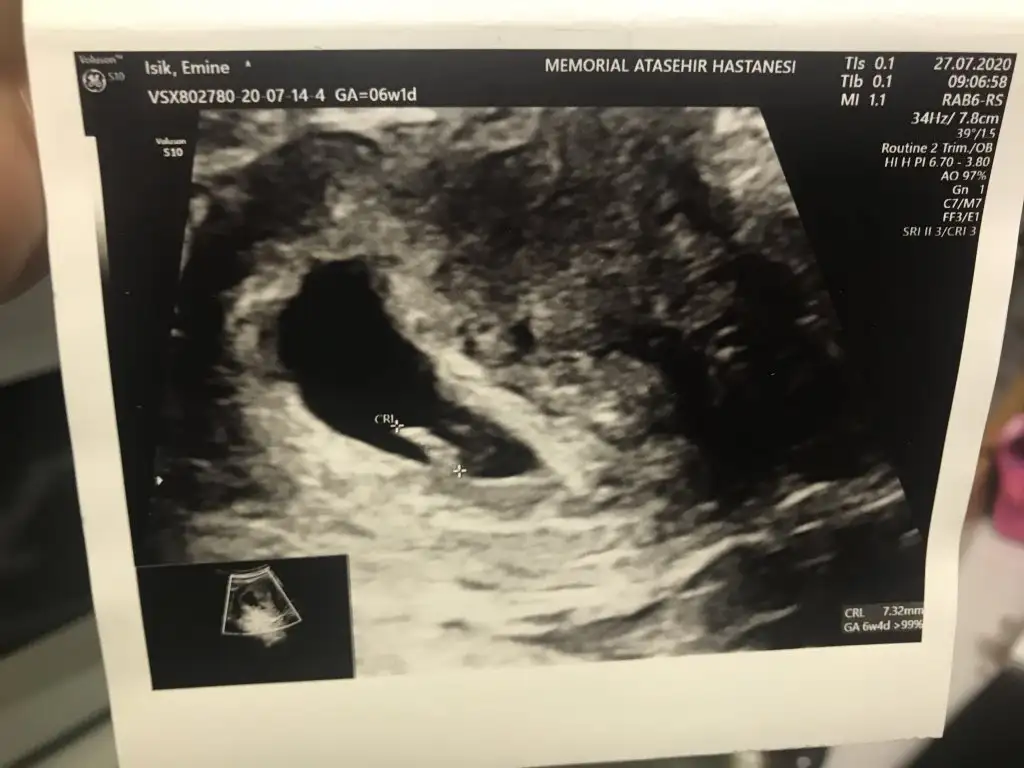

Karındansa erkek vajinal se kızMerhaba, bana da yorum yapabilir misniz? Teşekkür ederim

Çok teşekkür ederim. Aynı gün çekilmiş bir usg daha var. Orda da sağa yakın görünüyor.Karındansa erkek vajinal se kız

Demekki hareket etmiş yolk saç ne tarafta oluştuysa onu bilmek lazım bu teori için 6 7 haftalık görüntü lazımÇok teşekkür ederim. Aynı gün çekilmiş bir usg daha var. Orda da sağa yakın görünüyor.